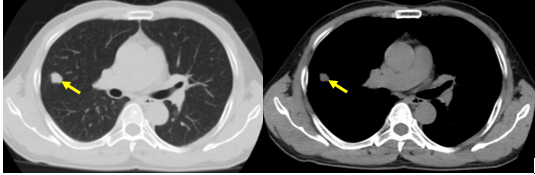

Hình 1. Hình ảnh chụp cắt lớp vi tính lồng ngực độ phân giải thấp phát hiện khối thùy giữa phổi phải, kích thước 14x15mm (mũi tên vàng)

Sau khi hỏi thông tin lâm sàng và khám bệnh, bác sỹ khám bệnh đánh giá bệnh nhân có nguy cơ cao mắc ung thư phổi với tiền sử hút thuốc lá >20 bao/năm. Sau khi chỉ định cho bệnh nhân chụp cắt lớp vi tính lồng ngực liều thấp, bác sỹ đã phát hiện bệnh nhân có khối thùy giữa phổi phải, kích thước 14x15mm, bờ không đều, có các dải xơ mảnh xung quanh co kéo nhu mô phổi, theo dõi u phổi.